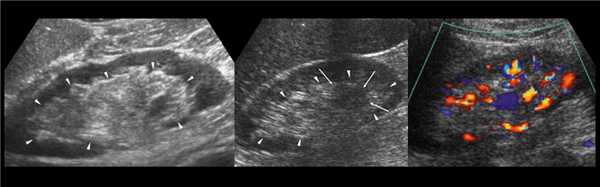

В марте 2002 г. в связи с эпизодом лейкоцитурии лечился у нефролога; при контрольном УЗИ впервые диагностированы изменения в мочевом пузыре и паравезикально слева. При повторном УЗИ выявлено (рис. 1а): правая почка увеличена в размерах (длина 12,7см; толщина паренхимы 1,6 см); чашечно-лоханочная система не расширена. Левая почка отсутствует. Стенки мочевого пузыря не изменены; в просвете слева определяется округлое образование 3,5 x 4,6 x 5,0 см с неоднородным содержимым (объем около 40 мл). Заключение: аплазия левой почки; уретероцеле слева.

а) Эхограмма.

Компьютерная томография (КТ): в проекции устья левого мочеточника и на фоне мочевого пузыря слева определяется дополнительная тень 3,1 x 4,0 x 4,0 см с четкими контурами и плотной стенкой. Мочеточник выше устья расширен до 1 см. Заключение: КТ-картина уретероцеле слева, уретерэктазия слева (рис. 1 б, в).